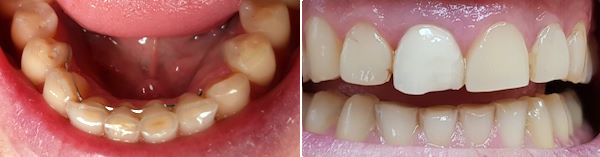

24-jähriger Patient (17.11.2025 / 8888)

Anamnese: Der Patient musste wegen einer kieferorthopädischen Behandlung 4+4 ziehen und 765+567 nach vorne verschieben lassen. Deshalb ist eine Minderbelastung des Kauzentrums 6-6 entstanden. Um besser kauen zu können, hat er nur noch links gebissen. Dabei ist aber +7 elongiert und ein Vorkontakt auf +-7 entstanden, der ihn störte. Er hat deshalb schon fünf verschiedene Knirscherschienen erhalten.

Therapie: Die mesialen Höcker des Zahnes 6- konnten ganz einfach mit Komposit erhöht werden.

Das Kaugefühl war dann sofort besser.

In der nächsten Sitzung wird auch noch der Zahn 5- erhöht, um das Kauzentrum noch etwas mehr zu vergrössern.

Vorbehalt: das Kaugefühl ist gut geblieben.

24-jähriger Patient (29.01.2026 / 8888)

Der Patient hatte nach der kieferorthopädischen Behandlung kein gutes Bissgefühl. Die Anfärbung zeigt, dass die wichtigsten Molaren 6-6 fast nicht belastet werden.

Mit Komposit wurde auf die Molaren 76-6 je ein Witzgall-Höcker aufgesetzt. Diese befinden sich nicht am gewöhnlichen Ort, sondern dort, wo sie den Biss am besten unterstützen. Bei der kieferorthopädischen Behandlung mussten die oberen Molaren etwas nach vorne verschoben werden und passten deshalb nicht mehr gut zu den unteren.